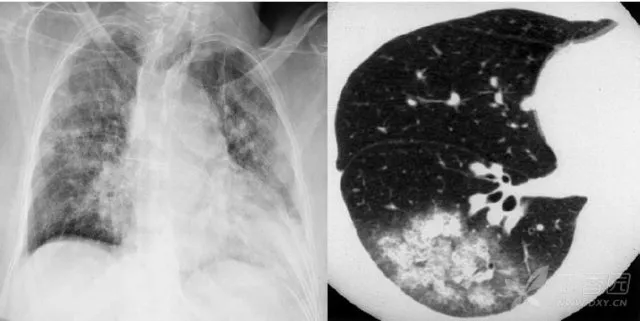

大葉性肺炎胸部影像

簡(jiǎn)單來(lái)講,肺炎出現(xiàn)較大的病灶,局限在一個(gè)肺葉,就叫大葉性肺炎。大葉性肺炎也叫肺泡性肺炎,這是因?yàn)榇笕~性肺炎的炎性滲出主要發(fā)生在肺泡。細(xì)菌、病毒、真菌、以及肺炎支原體等非典型病原體都可以引起大葉性肺炎。